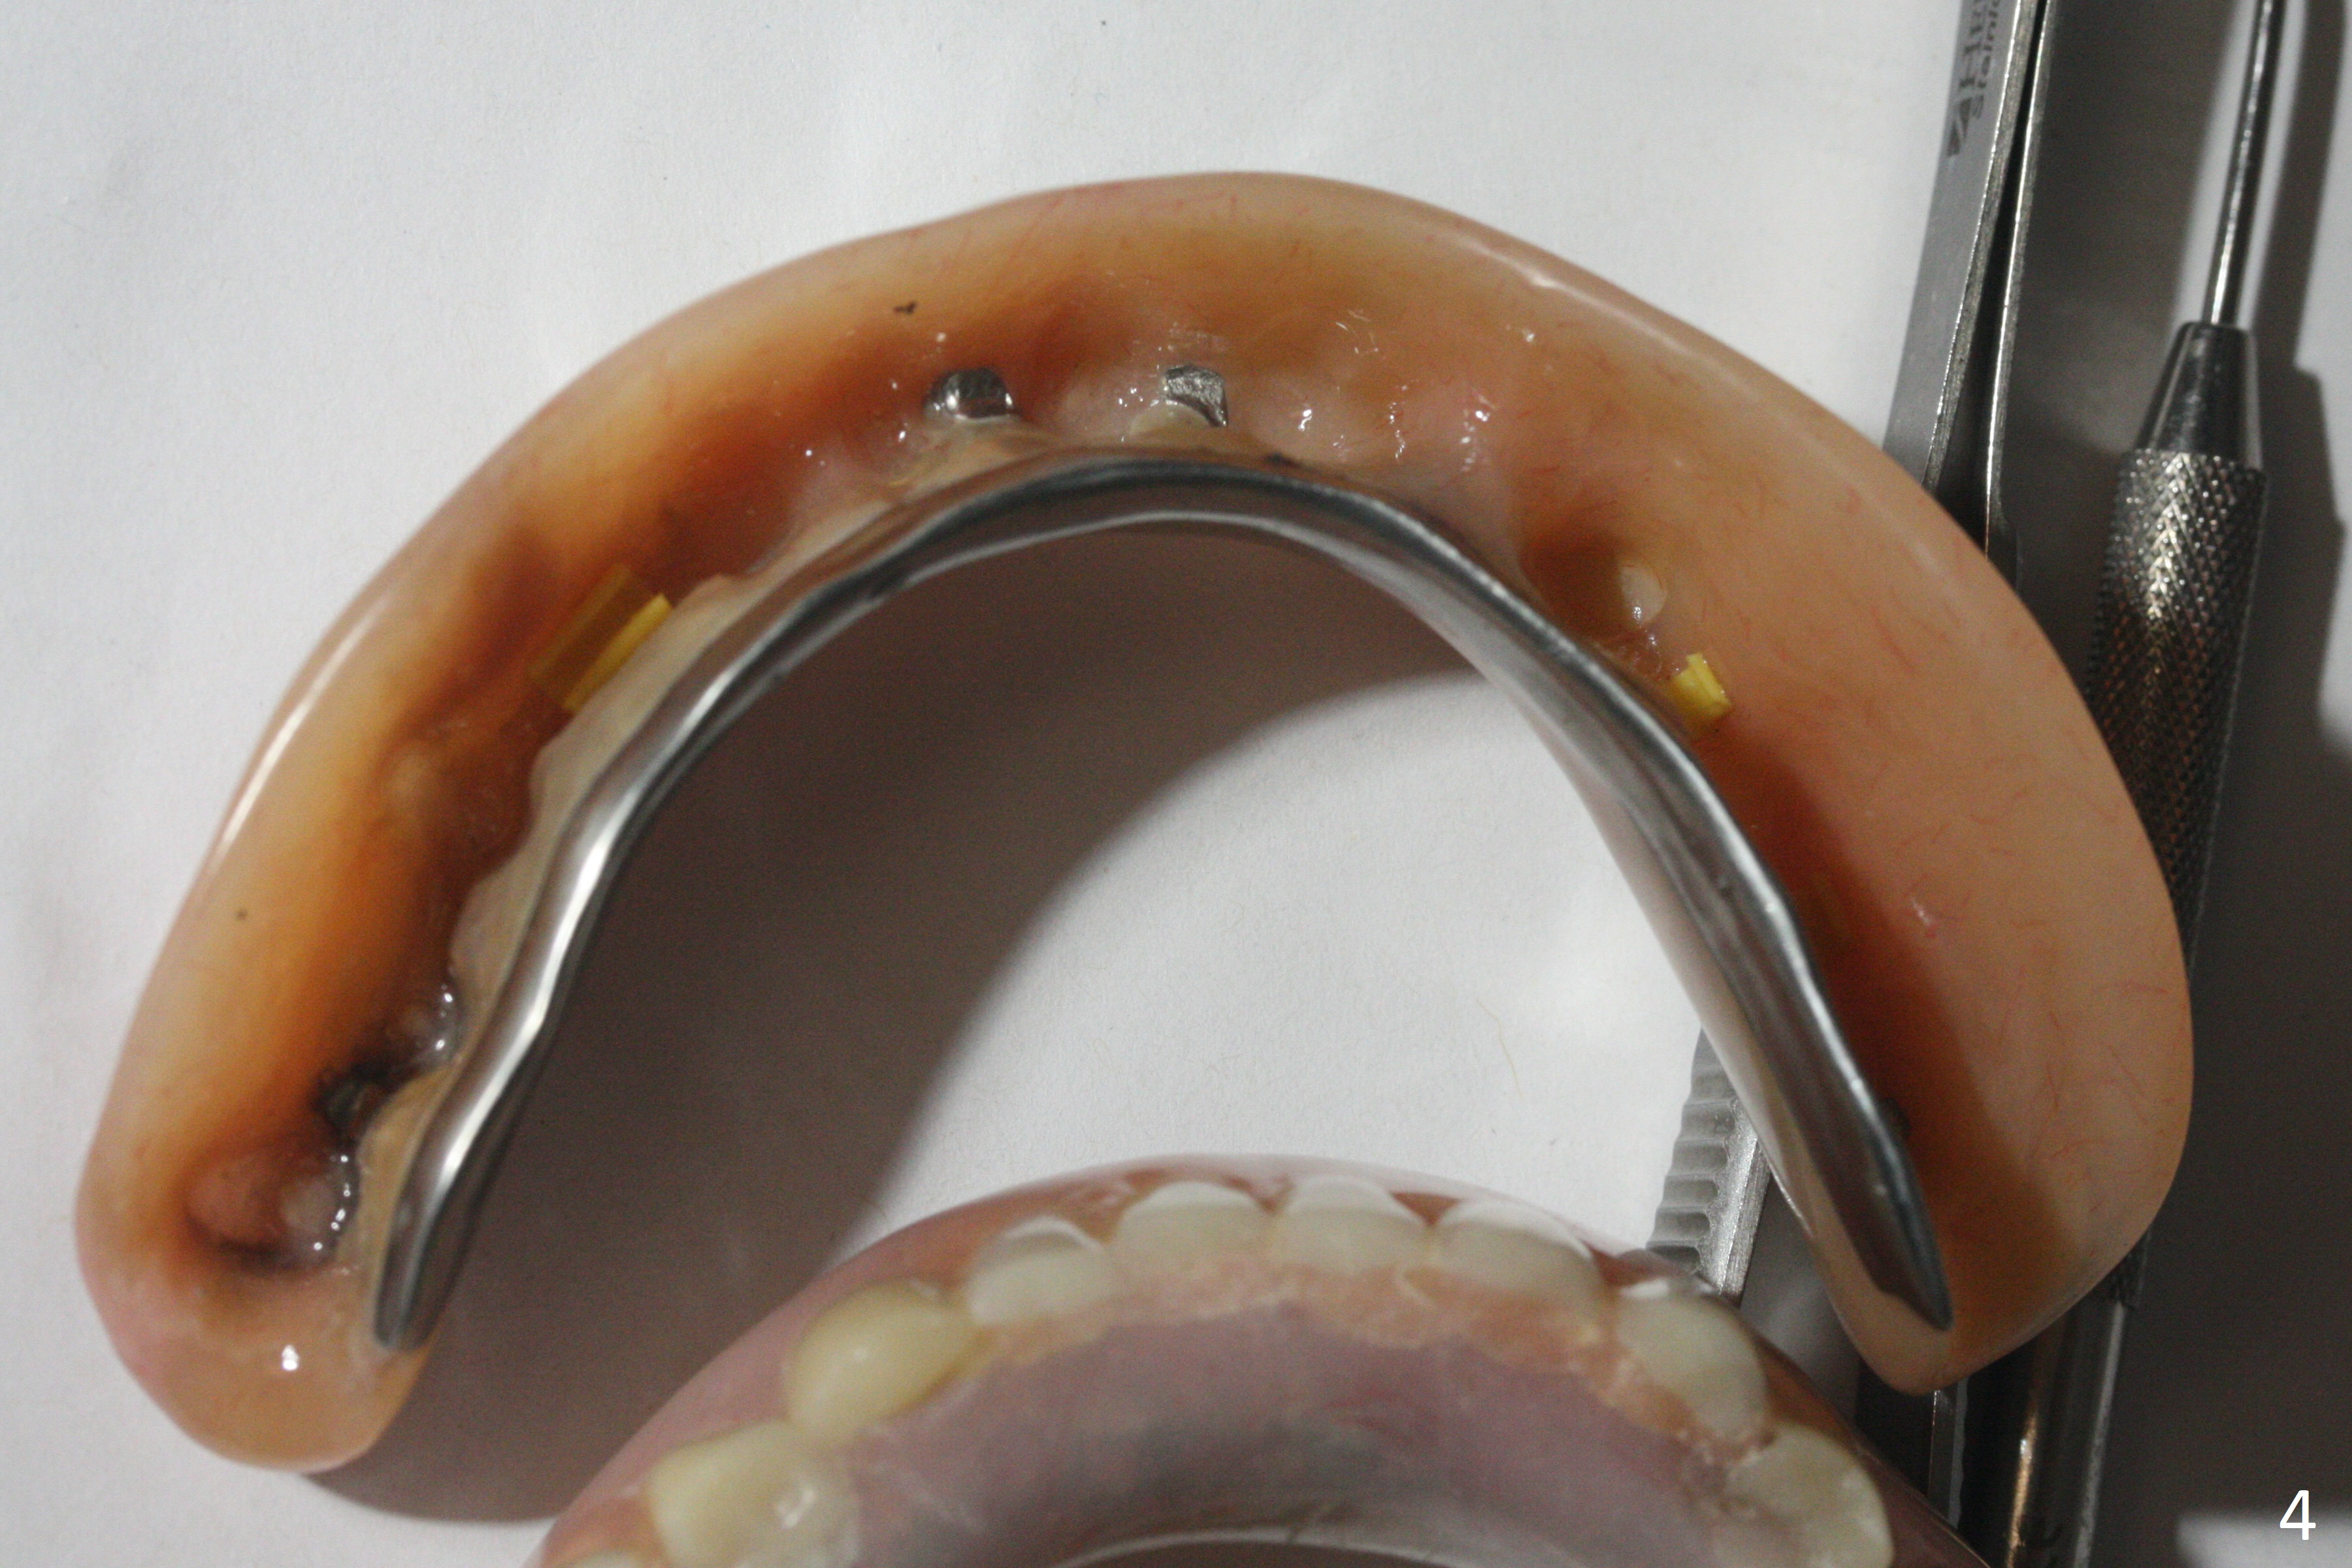

A 77-year-old man presents to clinic with chief complaint of loose lower denture, which is ~ 15 years old (Fig.1-6). The implants were placed ~ 30 years ago. There is wear and crack of the denture teeth (Fig.3). When the denture is remade, make metal occlusal surface at the premolar and molar region. An extra existing denture will be sent to lab for reference. What is the best method to take the lower impression? Block metal framework undercuts? Alginate or PVS?